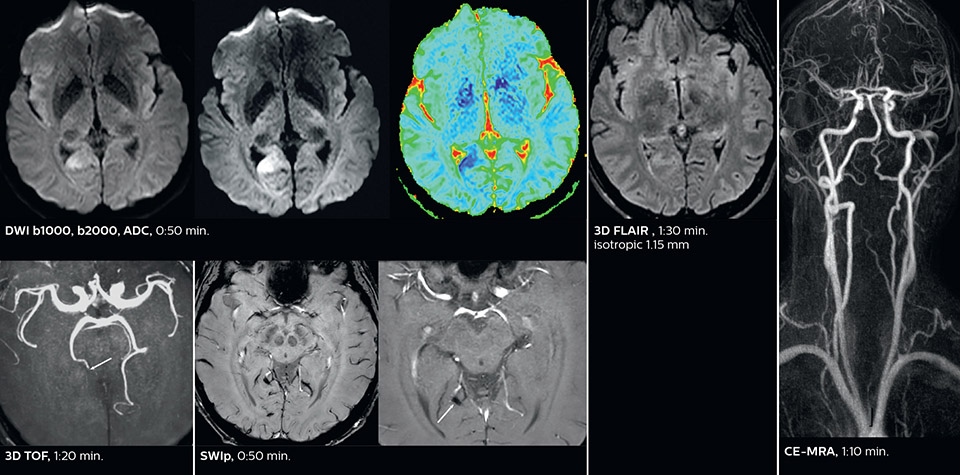

Dr. Savatovsky appreciates the improvements and flexibility that Elition with Compressed SENSE and MultiBand SENSE provides, particularly for stroke patients. “For stroke, it allows us to cut about 5 minutes off of our stroke protocol, or to keep the same acquisition time and get more insights.” The ability to perform more sequences can help in making a swift and confident diagnosis. “For example, our stroke cases usually include the regular sequences that every center does (b1000 diffusion, FLAIR, time-of-flight angiography), but we also image supra aortic vessels, and we can replace a gradient echo sequence with a fast 50-second susceptibility-weighted sequence, and all of this doesn’t add much time. because all the regular sequences are accelerated on Elition.” “The time savings with Compressed SENSE and MultiBand SENSE make it easier to add sequences to give us additional insights. Depending on the context and the first results, we might add a DSC perfusion to assess the ischemic penumbra, an ASL perfusion to help find an alternative cause in case of normal diffusion, or add a high-resolution T1 sequence for a stroke patient, to quickly assess wall imaging in emergency cases. The additional sequences can help improve patient management, because we can already consider some alternative diagnoses if the morphological MRI is normal.”

Using MultiBand SENSE allowed the staff to improve their diffusion quality. “Our diffusion sequence was already fast before, about 40 seconds. Now with Elition, it still lasts 40 seconds, but we improved the spatial resolution by 0.2 mm and use high b-values to be more sensitive to visualize changes related to acute stroke,” says Dr. Savatovsky. “We now also developed a high resolution DTI sequence (1.3 x 1.3 x 2 mm) that can be reformatted and takes 2 to 5 minutes depending on the coverage. We use it every time we have a doubt, or when we expect the diffusion to be abnormal but don’t see that on the fast sequence. We occasionally spot small ischemic infarctions that would not have been visible with the regular diffusion sequence.”

This is an example of acute ischemic stroke with distal occlusion of the right posterior cerebral artery. Note the improved visibility of the ischemic territory on the diffusion weighted image with high b-value. The 3D FLAIR shows a distal PCA occlusion. The fast SWIp depicts the thrombus on the isolated second echo image. The total scan time (including SmartBrain, preparations and a fast 3D T1w TSE Gd) is 8:00 minutes.